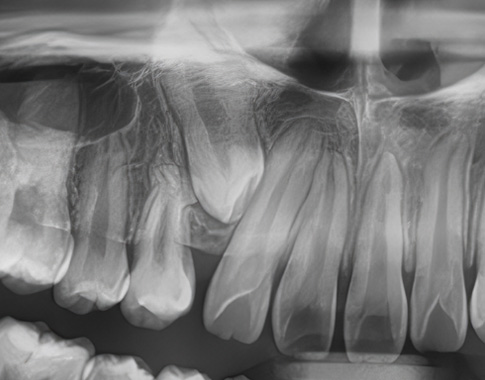

Impacted Tooth

숨어있는 치아교정,

매복치

매복치아나 늦게 나오는 치아 때문에 걱정되시나요?

교정치료를 통해 숨어있는 치아가 자연스럽게 나올 수 있도록 도와드립니다.

아이의 건강한 치아 배열을 위해 적절한 시기에 시작하세요.